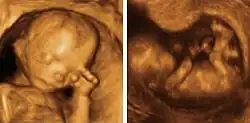

Medycyna

Metody obrazowania ciała ludzkiego stanowią element rutynowej procedury diagnostycznej oraz są szeroko wykorzystywane w badaniach naukowych. Do najczęściej wykorzystywanych technologii, które odtwarzają obraz wnętrza ciała na podstawie jego pewnych właściwości fizycznych, należy zaliczyć: ultrasonografię (USG), klasyczną rentgenografię (RTG), tomografię komputerową (CT), badania rezonansu jądrowego (MRI, fMRI) i tomografię pozytonową (PET-CT/PET-MRI). Chociaż istnieje również możliwość analizy poszczególnych wypreparowanych narządów i tkanek, zasadniczo techniki te wchodzą w zakres zainteresowań patologii.

Wizualizacja w szerszym znaczeniu obejmuje każdą próbę monitorowania przejawów życia. Zaangażowane są w to techniki medycyny nuklearnej, endoskopii, termografii, fotografii medycznej oraz mikroskopii. Wyniki wielu pomiarów, np. elektroencefalografii (EEG), magnetoelektroencefalografii (MEG), elektrokardiografii (EKG), które bezpośrednio są rejestracją pewnych arbitralnie przyjętych wartości, mogą być rzutowane na mapę ciała, w ten sposób również wchodząc w zakres metod obrazowych. Największymi zaletami praktycznie wszystkich wyszczególnionych badań jest niska inwazyjność (mimo iż sumaryczne dawki promieniowania bywają znaczne[24]) oraz łatwość w reprodukcji i przetwarzaniu wyników.